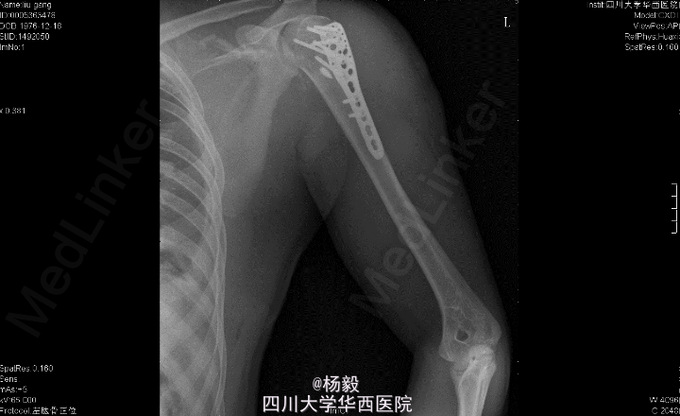

初步诊断:1、左肩胛骨粉碎性骨折。2、左肱骨外科颈骨折伴神经损伤。3、左侧胸腔积液闭式引流术后。4、左侧多发肋骨骨折。5、左肺挫伤。6、脾脾脏损伤? 全麻下行左肱骨外科颈骨折切开复位内固定术。

肱骨外科颈骨折的手术治疗策略是什么?